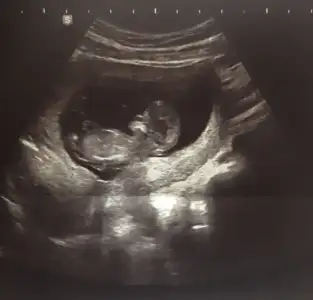

Üçüncüsü tüm vucüt